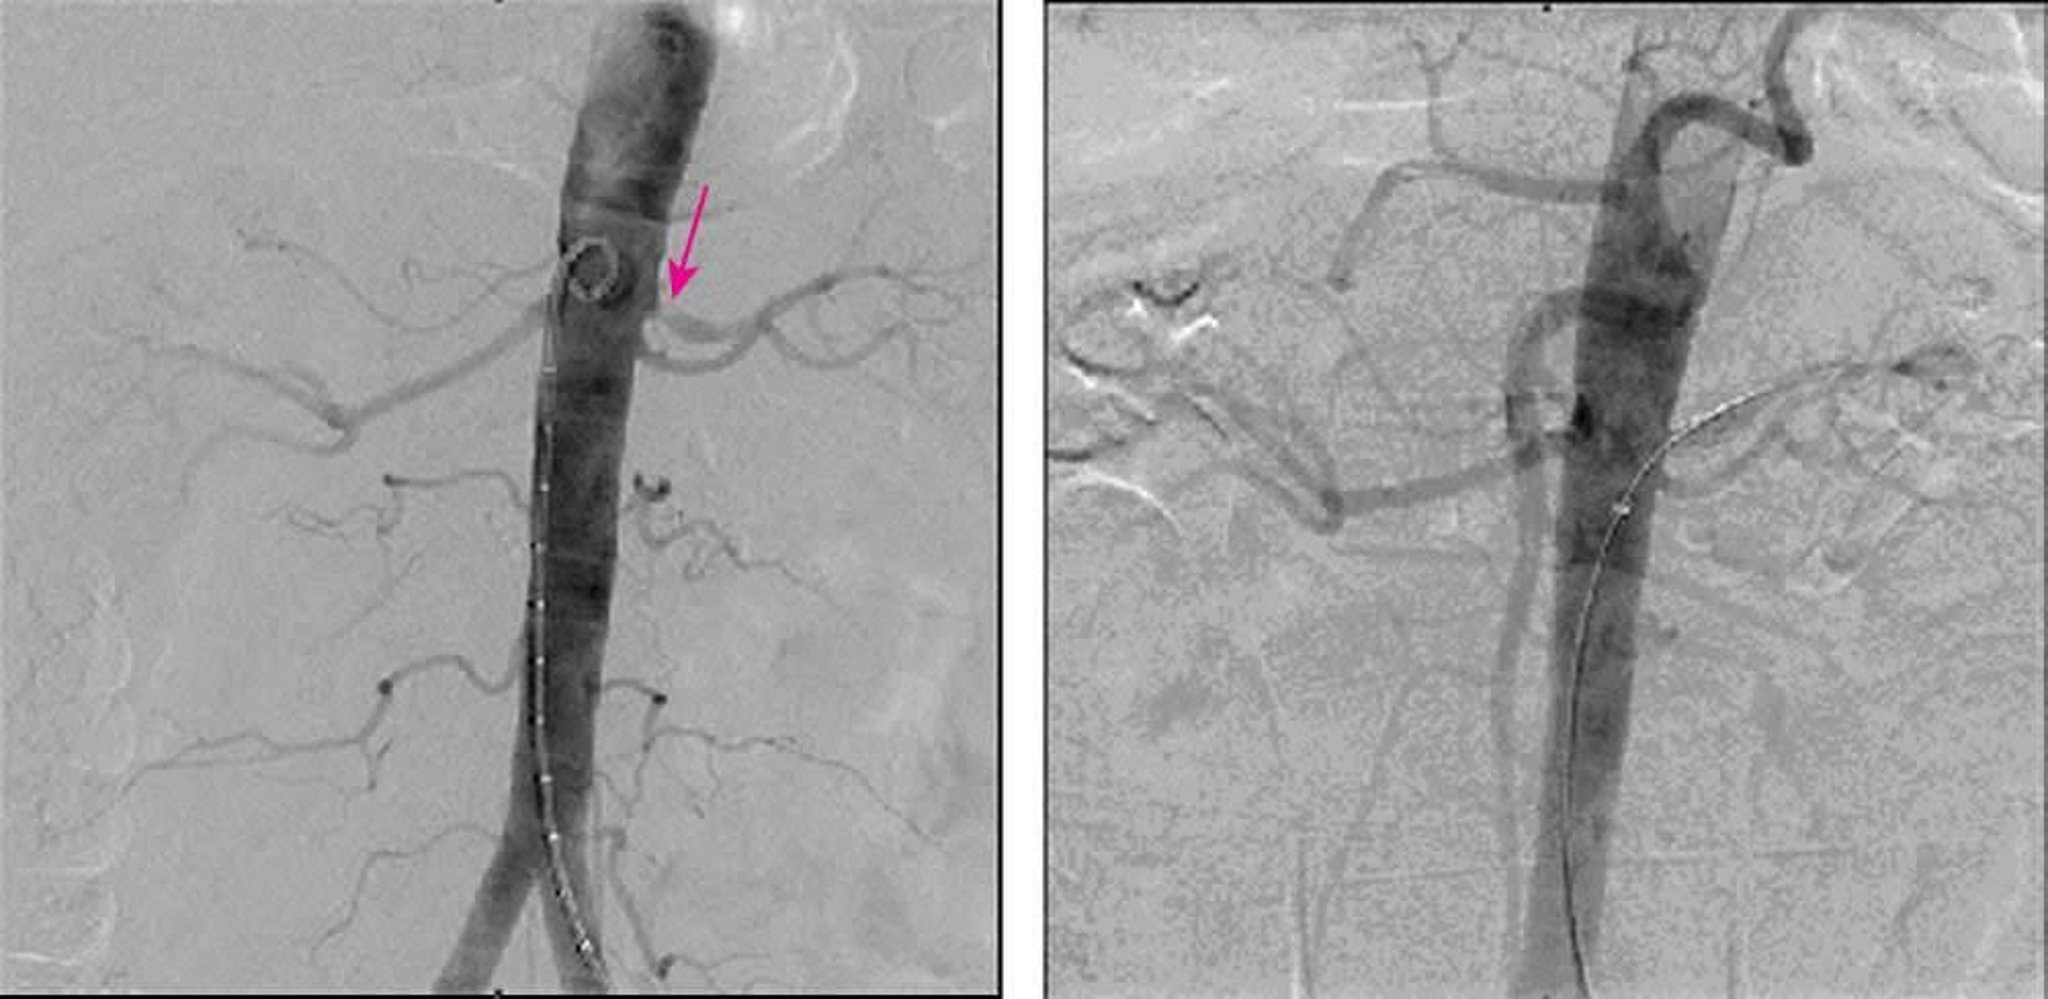

Estenosis de la arteria renal (angiografía por sustracción digital)

La imagen de la izquierda muestra una estenosis del 90% en el origen de la arteria renal izquierda en una angiografía por sustracción digital. La imagen de la derecha muestra la resolución completa de la estenosis después de la colocación de una endoprótesis.

Image provided by Jan N. Basile, MD.